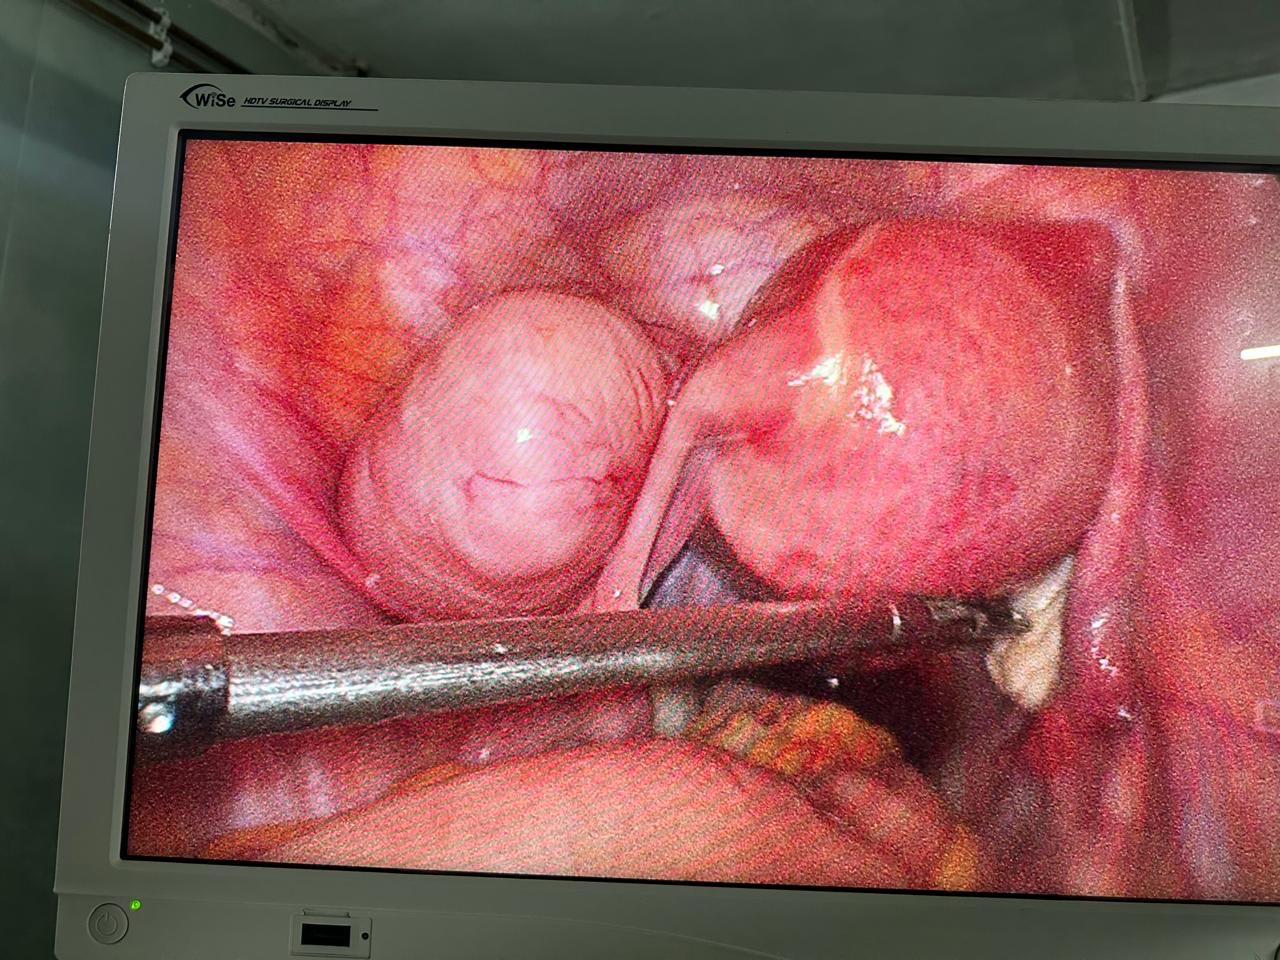

Laparoscopic and minimally invasive gynecological surgeries offer advanced, safe, and effective solutions for diagnosing and treating various reproductive health conditions. These procedures involve small incisions, specialized instruments, and a high-definition camera, allowing surgeons to operate with precision while minimizing pain, scarring, and recovery time. Commonly used for conditions such as ovarian cysts, fibroids, endometriosis, and ectopic pregnancies, these procedures provide quicker recovery and improved outcomes compared to traditional open surgery.

Advanced Surgical Technology

We use state-of-the-art equipment for high-precision, effective, and safe surgical outcomes.